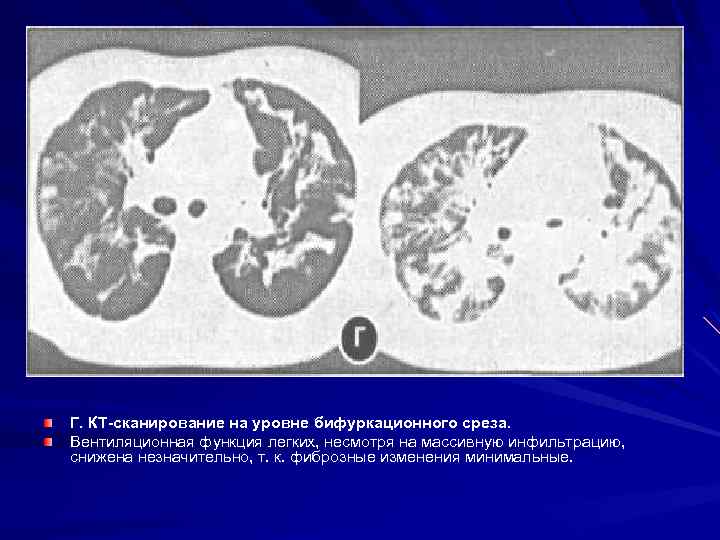

Рис. 6. Рентгенограммы органов грудной клетки больной экзогенным аллергическим альвеолитом. А. Рентгенограмма, выполненная на 3 й день от начала заболевания. Определяются шаровидные, местами сливные инфильтраты. Б. Рентгенограмма, выполненная через 2 недели от начала заболевания. Инфильтративных изменений стало значительно меньше, определяются мелкоочаговые уплотнения, интерстициальная инфильтрация и фиброз, корни широкие, малоструктурные. В. КТ сканирование органов грудной клетки. Через 3 недели от начала заболевания определяется массивная инфильтрация легоч ной паренхимы иинтерстиция.

Г. КТ сканирование на уровне бифуркационного среза. Вентиляционная функция легких, несмотря на массивную инфильтрацию, снижена незначительно, т. к. фиброзные изменения минимальные.